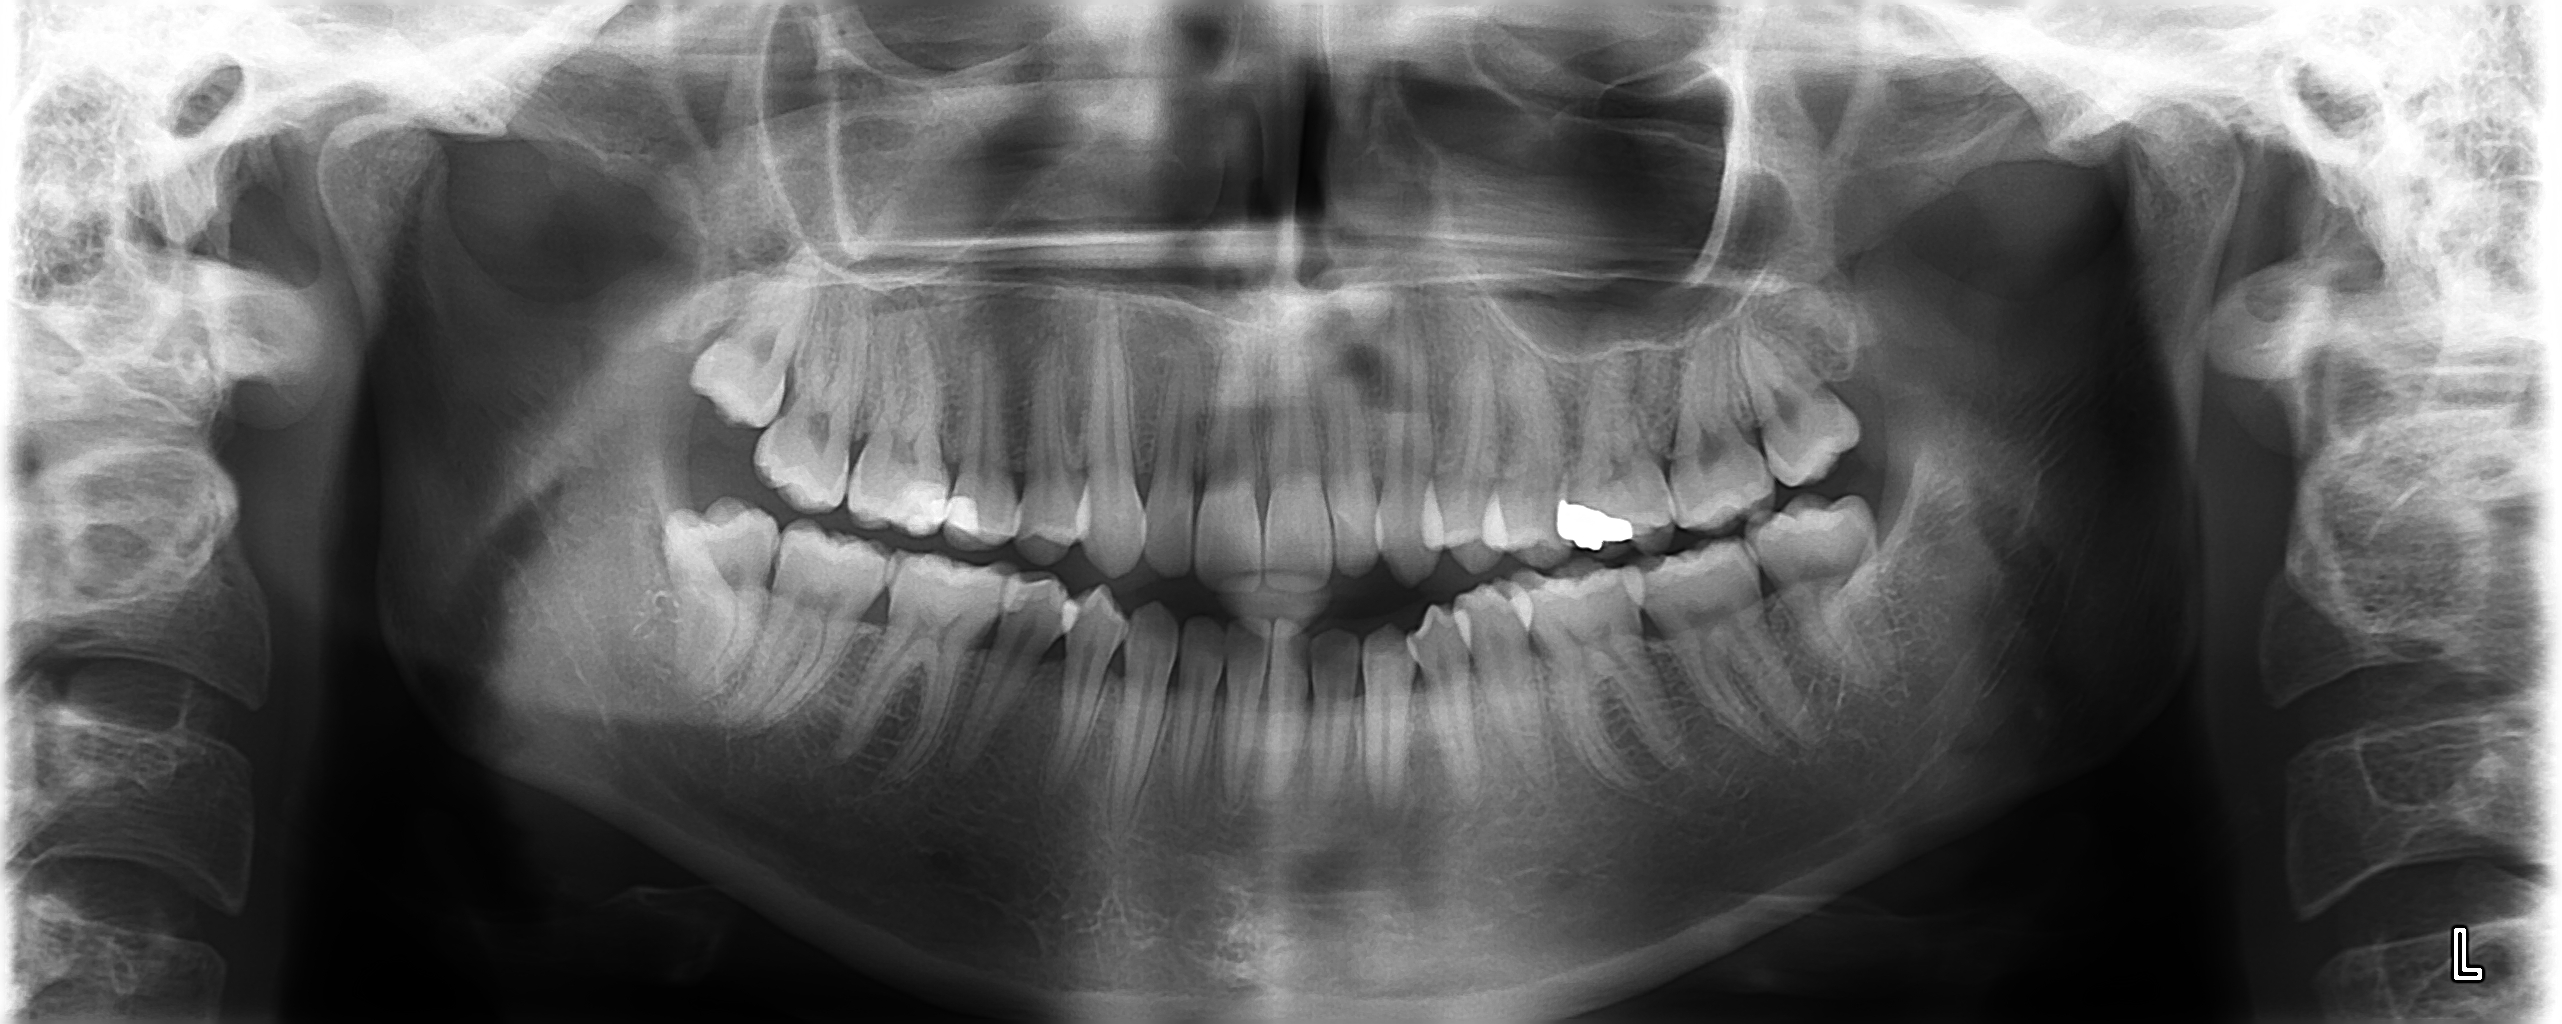

Avant l’établissement d’un diagnostic et d’un plan de traitement en orthodontie, un bilan clinique avec dossier d’étude est souvent nécessaire.

- l’interprétation de documents radiographiques réalisés à l’extérieur,